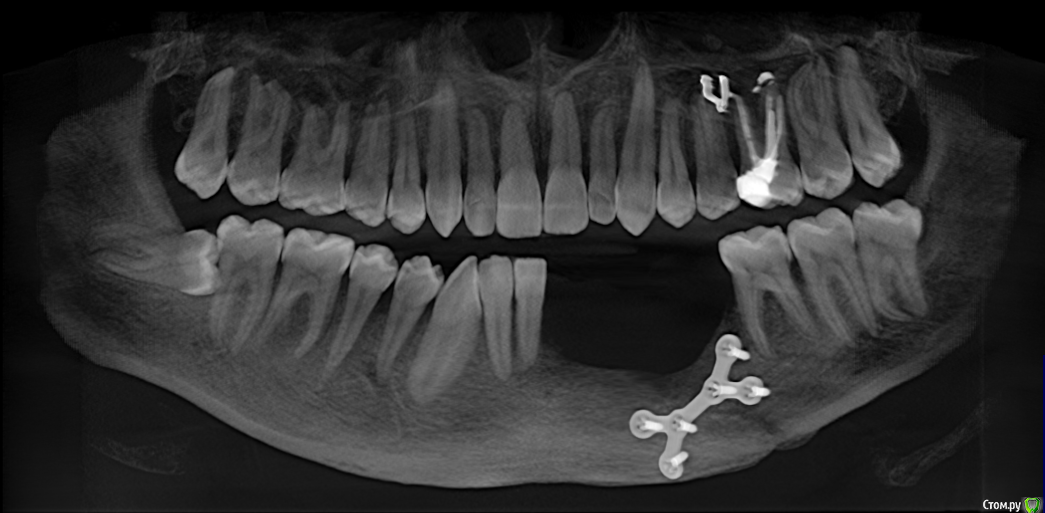

mikheil.osipov Опубликовано 16 декабря, 2015 Поделиться Опубликовано 16 декабря, 2015 Доброго времени сутокЧетыре месяца назад, 2-го августа, я попал в аварию и получил перелом нижней и верхней челюсти. На нижней челюсти был односторонний открытый перелом, а также перелом альвеолярного отростка с 1-го по 5-й зубы. Также был поврежден нерв, потеря чувствительности левой части губы и подбородка. Мне сделали операцию – на нижней челюсти провели остеосинтез титановой пластиной, альвеолярный отросток закрепили шинами, а на верхнюю наложили шов проволокой. По какой то причине нижняя челюсть пложо заживала, альвеолярная кость местами была оголена и даже был виден край ушка пластины, врач назначил солкосериловую мазь, один раз сделал пластику, но кость опять оголилась. Врачь сказал, что начался некроз (странно, но температуры и гноя не было) и 20 октября удалил отломонный отросток. После удаления прошло почти два месяца, 4 месяца после перелома, 6 декабря я снял томографию и вроде бы заживление идет нормально, но теперь у меня проблемы с дальнейшей имплантацией из-за недостатка костной ткани. Мне 25 лет и хотелось бы востановить утраченные зубы с учетом качества и долговечности. Возможно ли установить импланты и нужно ли для этого наращивание кости? Прошу подскажите какой будет оптимальный метод протезирования в моем случае? Ниже я выкладываю старую и новую 3D томографии и фото. Томография и фото до удаления:Ссылка на томографию: https://drive.google.com/open?id=0B4pglooYIfg_TXJSUXVEQ2p0b2c Последняя томография и фото:Ссылка на томографию: https://drive.google.com/open?id=0B4pglooYIfg_aVhLSHRobkZHdzA Заранее спасибо! Ссылка на комментарий

mikheil.osipov Опубликовано 17 декабря, 2015 Автор Поделиться Опубликовано 17 декабря, 2015 Так было до удаления: Вот панорама и снимки: Ссылка на КТ https://drive.google.com/open?id=0B4pglooYIfg_aVhLSHRobkZHdzA Я был на консультации и мне сказали что нужна пластика искуственной костью и каркасом. Также сказали, что верхние винты могут помешать при имплантации и их надо будет снять. Врачь сказал, что ситуация сложная, также недостаток мягких тканей создает проблемы. Возможно ли обойтись без каркаса? Ведь его установка и у даление дополнительная травма и есть риск осложнений. Возможно ли установить импланты более простым методом? Ссылка на комментарий

mikheil.osipov Опубликовано 18 декабря, 2015 Автор Поделиться Опубликовано 18 декабря, 2015 Спасибо Вам за отзывы. А в чем заключается сложность с гигиеной в этом случае? Зубы будут сниматься с имплантов и их надо будет чистить как протез?Сколько имлантов можно установить без костной пластики и приблизительно как долго они мне праслужат? Мне сказали что без наращивания кости можно установить только два импланта и с ними надо будет аккуратно оброщаться, а в случае наращивания поставят три, а на них мост. Меня волнует наращивание кости, ведь процедура не простая и нужно время чтобы все срослось, есть определенные риски. Конечно, востановить утраченную кость будет отлично, но всеже поскажите какие приемушества мне даст костная пластика? Как поведет себя зубной ряд и челюсть со временем если оставить такой дефект и прямо поставить импланты? Как долго продержится первый зуб? Также меня интересует вопрос пластины. Мой врачь говорит, что кость приросла к винтам и снимать ее нельзя, хотя некоторые врачи говорять что снимать нужно после того как кость срастется. В интернете тоже разные мнения по эмоту вопросу. Мне всеже хотелось бы снять ее, ведь после сростания она будет не нужна и со временем может создать проблемы. К тому же верхний край пластины просвечивается через слизистую. Что вы считаете по этому поводу? Можно ли снять пластину и можно ли совместить это с костной пластикой? И еще, нужно ли удалять шов с верхней челюсти? Вот еще снимок с 3Д: Спасибо заранее! Ссылка на комментарий